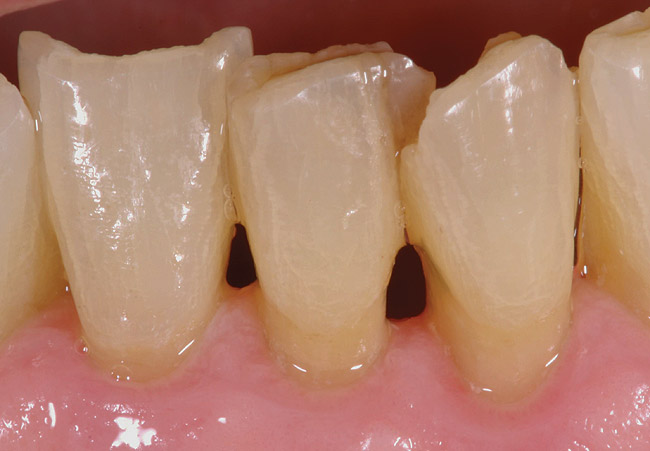

Stage 1 Remineralization (R1)

R1 root surfaces (Figure 5) appear yellow and shiny upon visual inspection. In addition, the root surface will feel smooth, hard, and glass-like upon gentle exploration with the side of the explorer. The fluoride, calcium, and phosphate that remineralizes these root surfaces leaves them with a decreased risk for stain, sensitivity, and decay. No restoration is necessary for a patient with R1 root surfaces.

It is the experience of the authors that these patients present with sensitivity that is greatly reduced or eliminated. This greatly improves the oral health-related quality of life for such patients, as these positive results provide them with a restored or improved perception of their oral health and comfort. Moreover, these patients generally prefer to remain on the remineralization protocols indefinitely due to the noticeable positive impact from the remineralization protocols. This has resulted in increased profitability, patient retention, and referrals for the private practice.

Figure 6  Although discolored, the root surface on the mandibular left first premolar is shiny and will feel hard, smooth, and glass-like when palpated with the side of the explorer. No restoration is necessary.

Figure 6